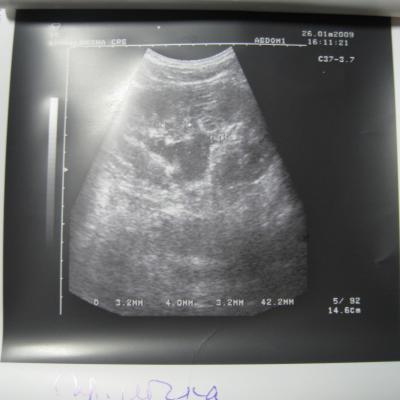

Доктор здраствуйте! мне 23 годаОколо полугода назад лежал на обследовнии в нефрологии,где был посиавлен диагноз:хр,пиелонефрит обеих почек,МКБ,микролиты обеих почек 2-4мм,наиболее крупный справа 4 мм!Было рекомендовано:курсам пить пролит,цистон,урологические сборы и тд!Все ето я принимал,почки особо не беспокоили если тока изредка небольши тупые боли в пояснице по утрам и все!Вчера решил сделать узи почек:диагноз был поставлен следующий:гидронефроз правой почки 1 степени,(врач сказал что лоханка в правой почке увеличена до 40 мм из за МКБ,лоханка левой почки 18 мм,остальные параметры в норме)микролиты обеих почек 2-4 мм,хр,пиелонефрит обеих почек особых жалоб у меня нету на данный момент!количество мочи в течении дня нормальное,удалось сдать анализы мочи(общий и по Нечипаренко.В общем анализе обнаружили немного белка,если нужны цифры могу написать завтра,но сказали что не очень много)по Нечипаренко все в норме!Более полное обследование чем узи нет возможности сделать!уролог прописал пить цистон ,уролесан и сборы трав пить и все!посоветуйте что нужно и можно делать в моей ситуации!снимок узи:

http://www.filehoster.ru/files/cc5720!Cпасибо